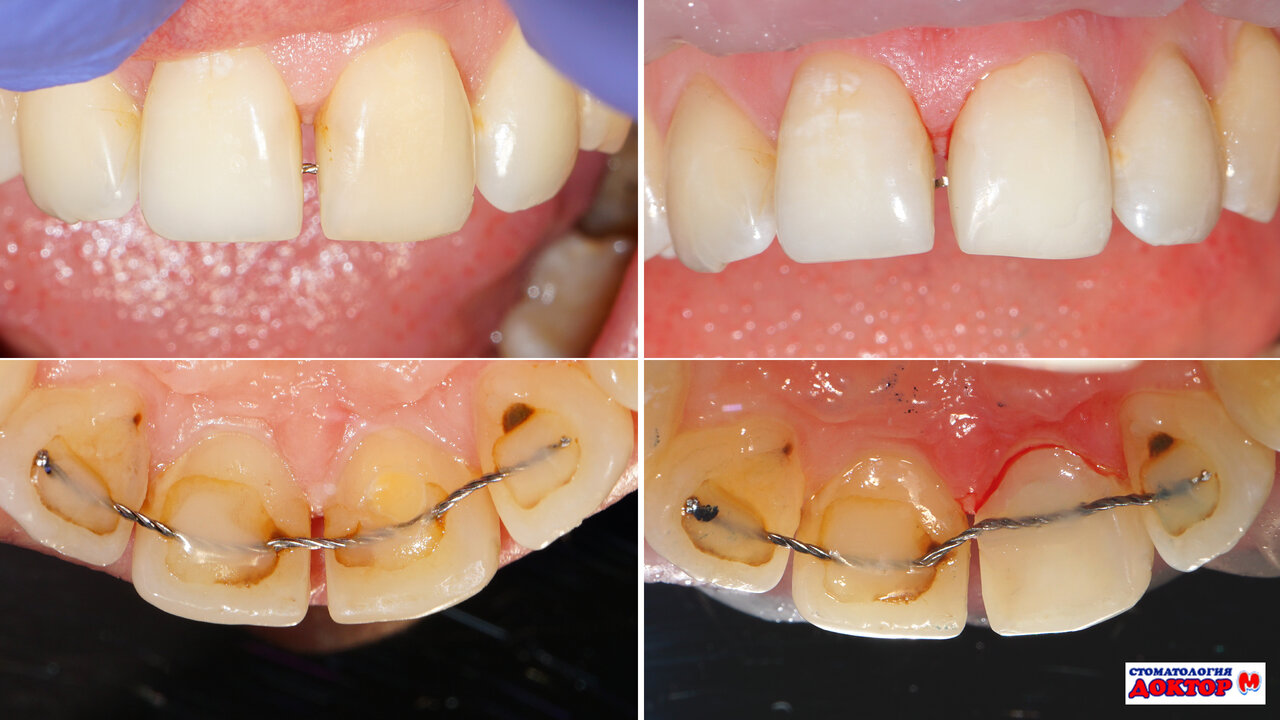

Обратилась в стоматологию Доктор М по рекомендации коллеги, был кариес между двумя передними зубами — поэтому искала хорошего врача. Результат превосходный, выполнено идеально — нет отличия от других зубов — качественно и профессионально! Также, в итоге вылечила остальные зубы у Рустам Робертовича. Спасибо Р.Р. и девушкам ассистенткам за чуткое и внимательное отношение. Даже не сомневайтесь! От сюда вы уйдёте довольными, с красивыми и здоровыми зубами!!!